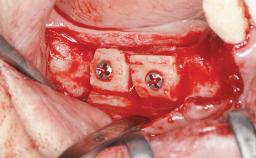

| Bone Augmentation | Horizontal|Sinus Floor Elevation|Staged|Vertical |

| Augmentation Materials | Autogenous chips|Autogenous block(s) |